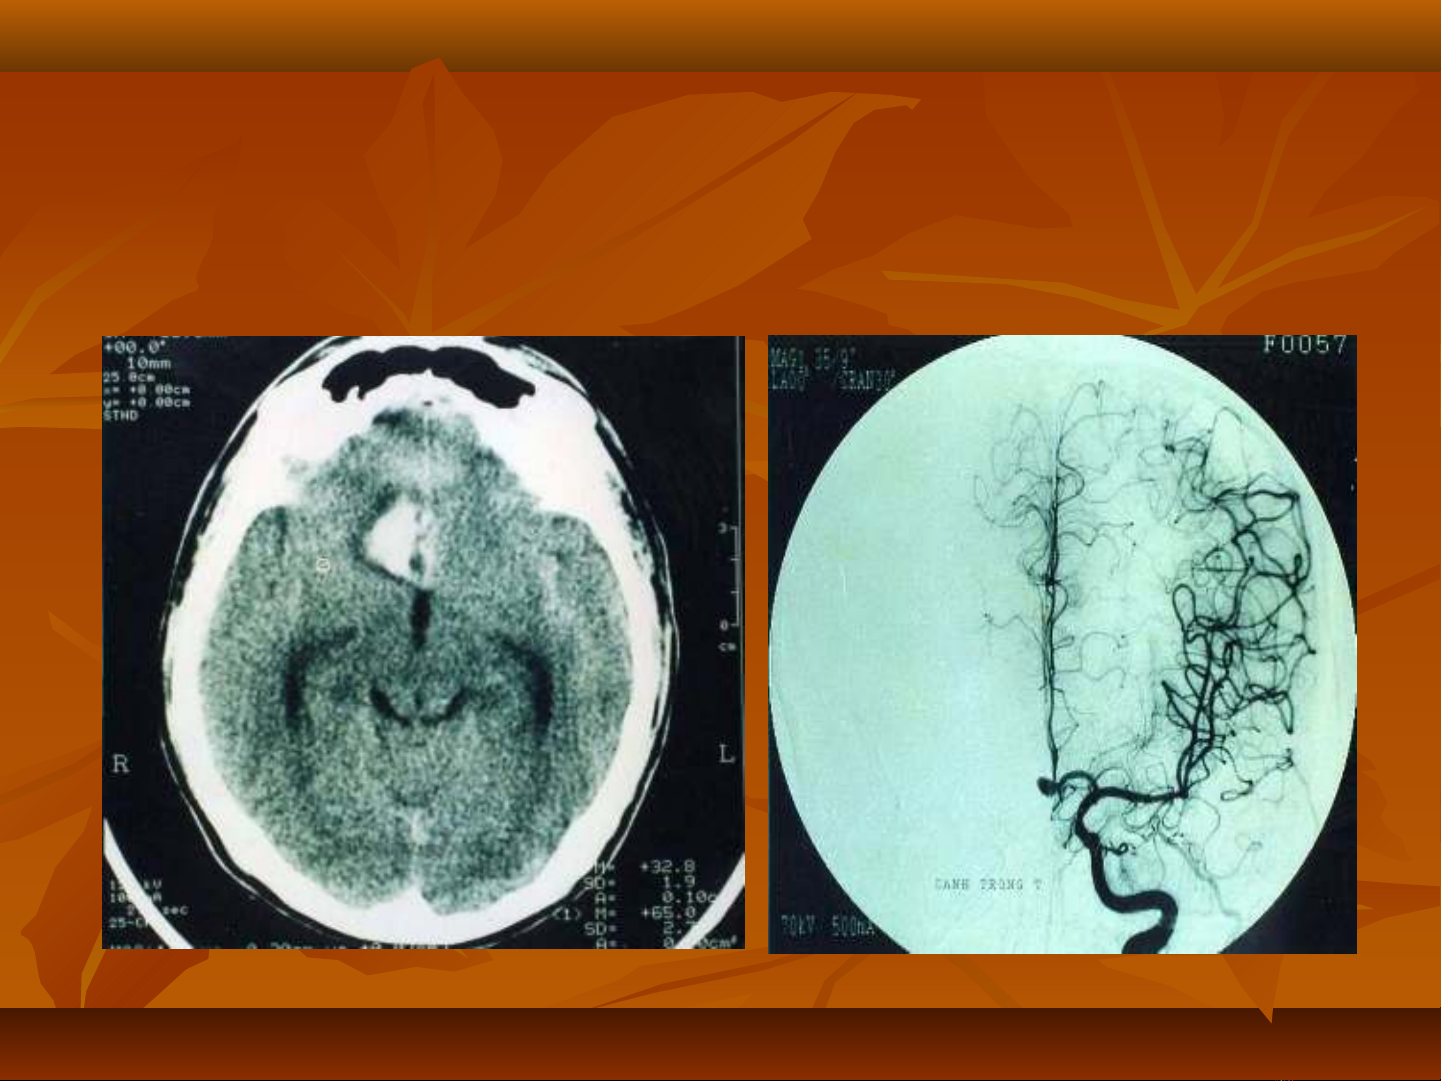

-Xu t huy t não: v m chấ ế ỡ ạ

Xu t huy t não: v m chấ ế ỡ ạ

-Nh i máu não: t c m ch ồ ắ ạ

Nh i máu não: t c m ch ồ ắ ạ